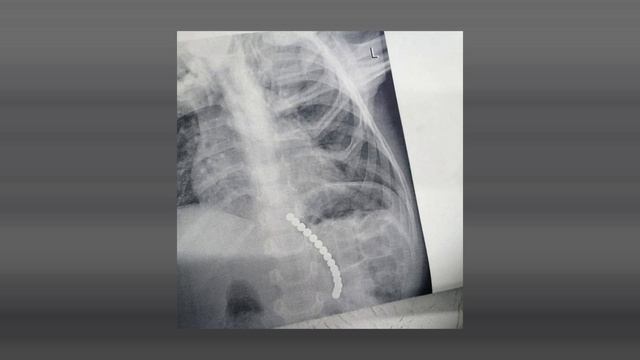

Телеграм канал t.me/orenburg_tg Сегодня у дежурной смены эндоскопистов Центра детской хирургии Оренбурга была непростая ночь. Врачам пришлось доставать крупные бусины из желудка 3-летнего ребёнка. По данным Минздрава, хирурги извлекли 15 магнитов. Сообщается, что маленького пациента доставили из Сорочинска. За оперативную работу в Министерстве поблагодарили врача ОДКБ Милюкову и медсестру Ушакову. Источник:https://1743.ru/news/60085-vrachi-orenburga-dostali-15-magnitov-iz-jeludka-3-letnego-rebenka